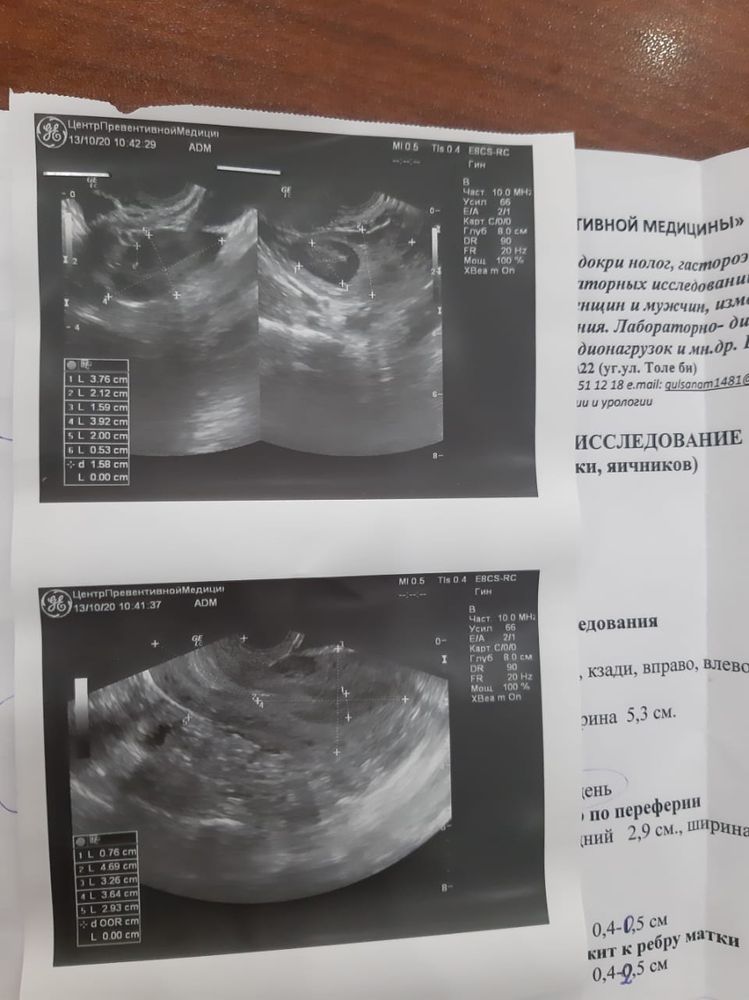

Подтянутые яичники

Подтянутые яичники 114 фотографий